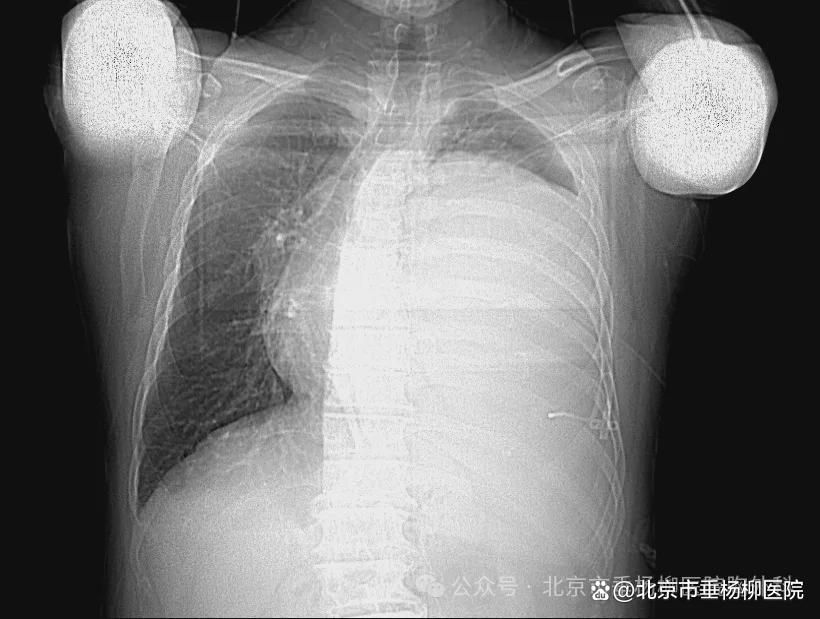

热灌注前